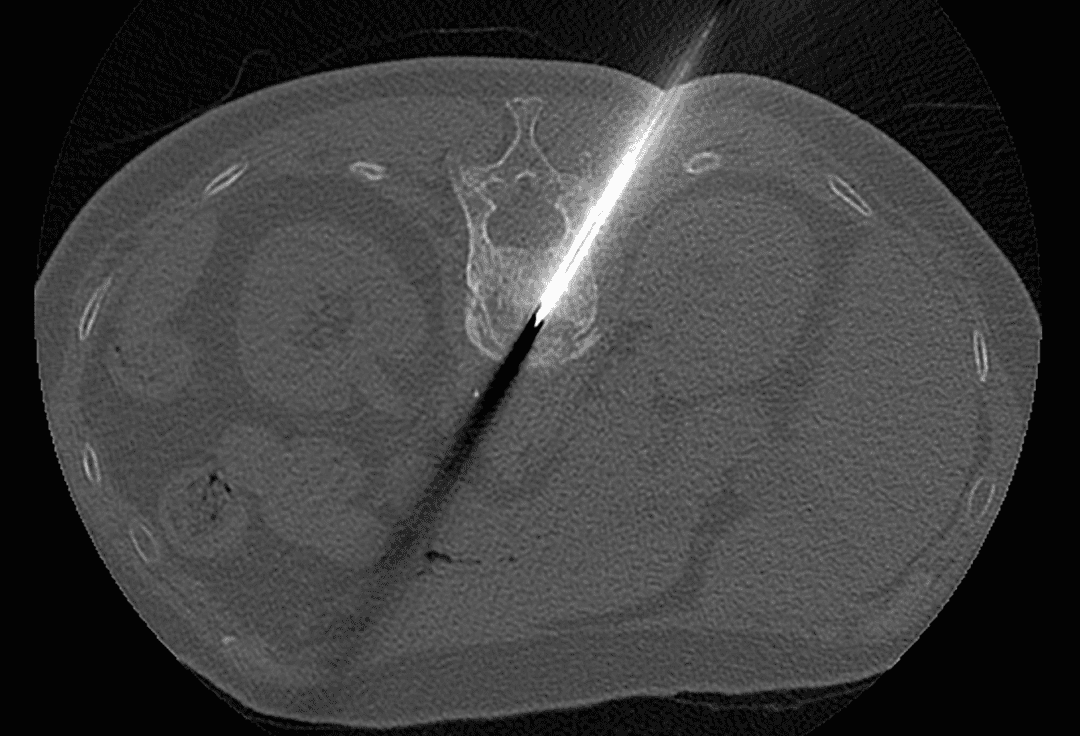

Positionnement de l'aiguille sous guidage

Résultat après injection de ciment

Injection du ciment

Une fois l’aiguille positionnée correctement, le ciment acrylique est injecté de façon contrôlée. Cette étape cruciale, suivie en continu grâce aux images, garantit une distribution homogène du ciment tout en minimisant le risque de fuite hors du vertèbre.